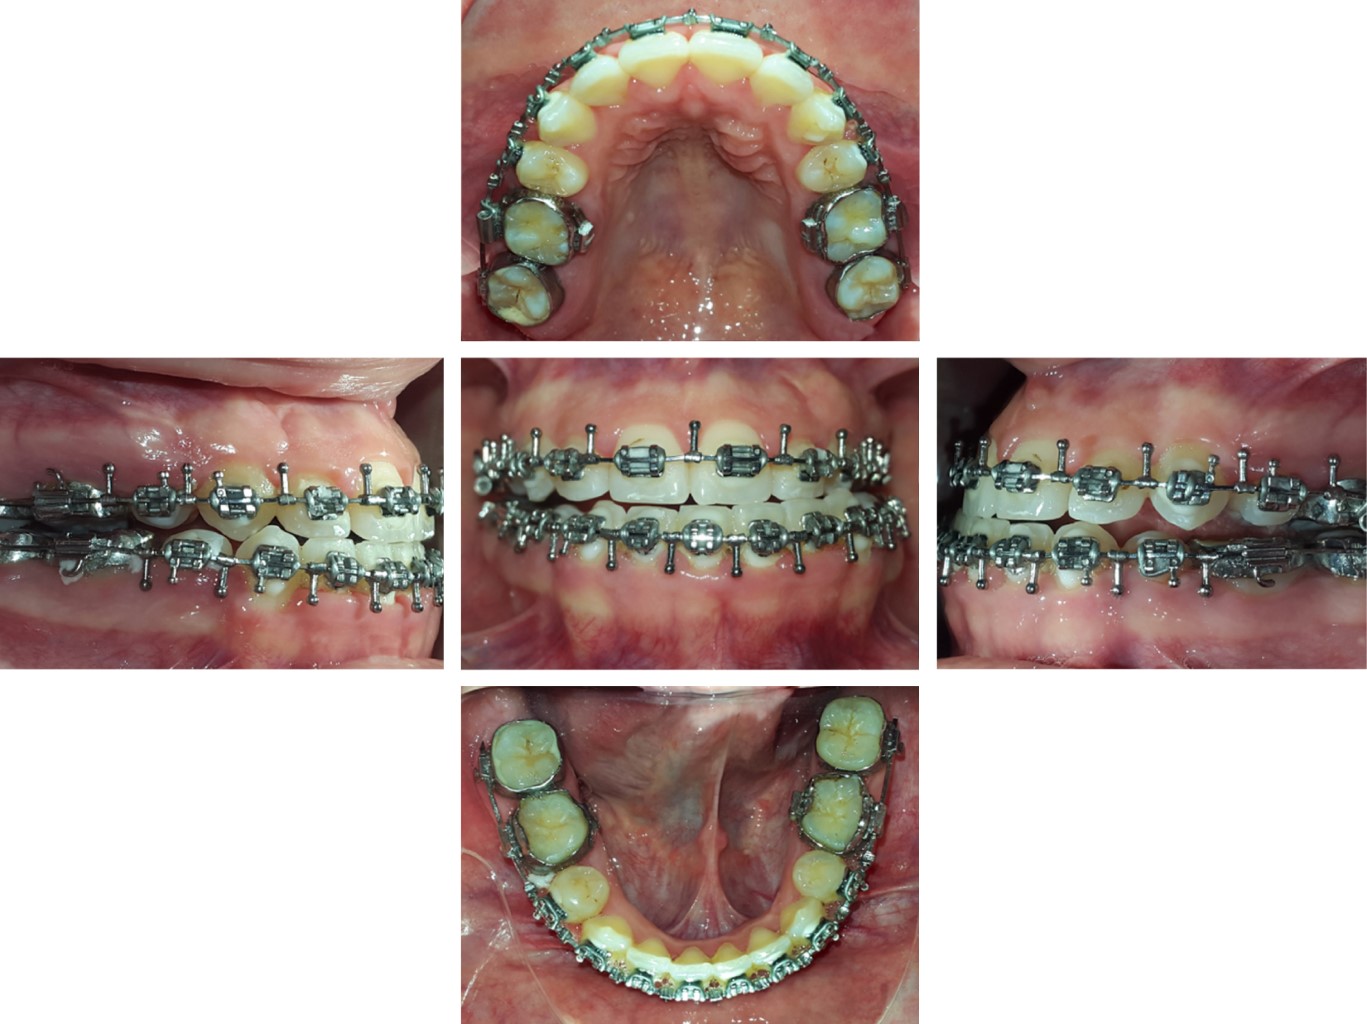

• Before surgery, surgical hooks were placed in the upper and lower arches 0.017" × 0.025" steel (Figure 4).

• 2. Surgical phase: maxillary impaction and advancement; mandibular retroposition and correction of laterognathia (Figure 5).